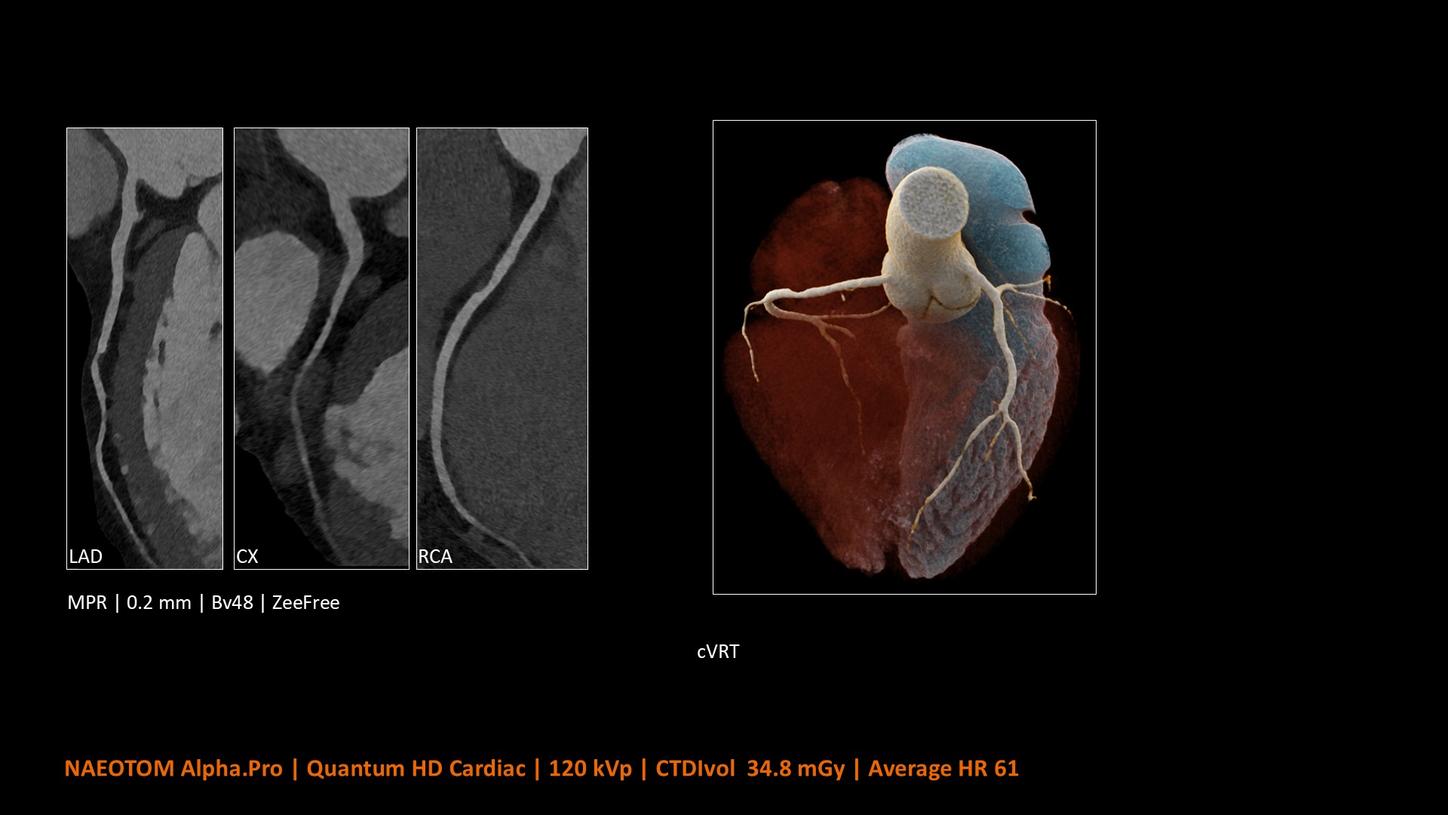

NAEOTOM Alpha® con Quantum Technology®, la nostra nuovissima Dual Source photon-counting CT, offre immagini Quantum HD Cardiac con uno spessore di slice di 0,2 mm. In questo modo è possibile visualizzare dettagli del cuore precedentemente non rilevabili senza incrementi di dose. Inoltre, le informazioni spettrali sono automaticamente disponibili in ogni scansione grazie a un processo di conversione diretta che trasforma i singoli fotoni dei raggi X in un segnale elettrico per creare l'immagine.

Quantum Technology consente una migliore valutazione diagnostica dei vasi coronarici nella TC. Secondo un recente studio, NAEOTOM Alpha e Quantum HD Cardiac potrebbero aver contribuito a ridurre la necessità di un'angiografia coronarica invasiva per il 54% dei pazienti nel rilevamento della malattia coronarica in una popolazione ad alto rischio.¹

Il Dott. Bálint Szilveszter, MD, PhD, presso la Semmelweis University a Budapest, in Ungheria, condivide I benefici dell’elevata risoluzione spaziale e della valutazione della placca con la TC photon counting e come questi permettano una maggior confidenza diagnostica nella valutazione dei disturbi alle coronarie (CAD)